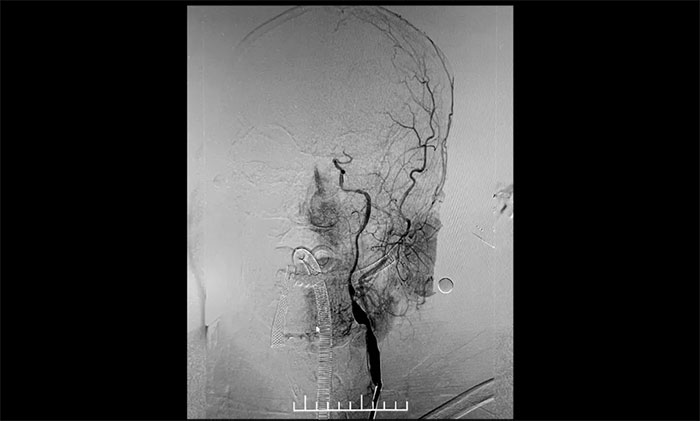

▲ 左颈内动脉起始段重度狭窄,并串联多处狭窄、闭塞

术后一个月,经过综合治疗,患者病情稳定。10月11日,再次行经皮左侧颈动脉慢性闭塞开通术,脑保护伞下左侧颈动脉支架置入手术,经皮左侧颈动脉球囊扩张成形术。术中造影显示,左颈内动脉起始段多发重度狭窄,左颈内动脉前向血流慢,左颈内动脉岩骨段中度狭窄,左颈内动脉眼动脉段、后交通段多发重度狭窄伴次全闭塞。

对于长节段颈动脉慢性闭塞再通,血栓逃逸是一个很重要的问题。由于患者左侧颈内动脉多处串联病变,闭塞段血栓负荷量大,保护伞无合适着陆位置,手术风险极大,难度极高。